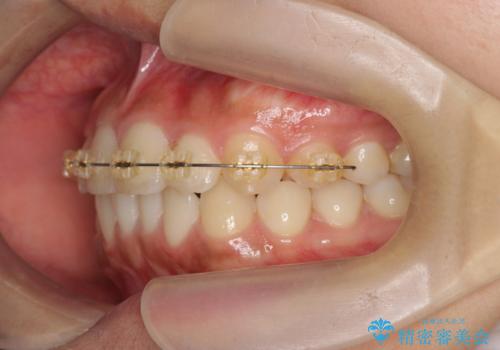

インビザラインによる矯正治療を行いますが、クロスバイトの改善をワイヤー部分矯正で事前に行うことにより治療期間の短縮する治療計画を立案します。

上下すれ違った噛み合わせはマウスピースでは改善に時間がかかり、またねじれが残ってしまうことも多々見られます。

マウスピース矯正を行う前に、これらの症状の改善の得意なワイヤー部分矯正を行うことで治療期間を短縮し、確実にすれ違いを改善することができます。